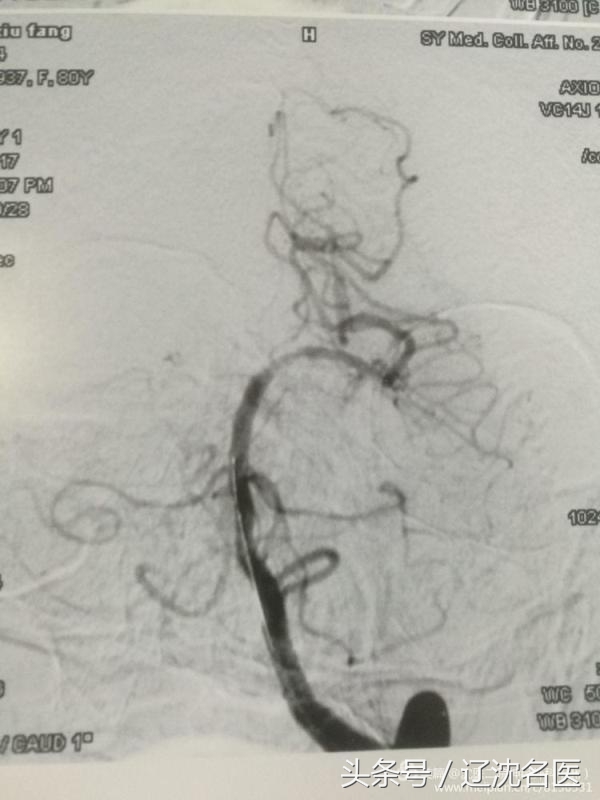

此时的患者心率上升到125次/分,血压190/115mmhg。因患者病情危重,静脉溶栓已经超过了时限,如果采用血管介入机械取栓,尚有一线希望。主治医生赵云东在争得家属同意后,立即将患者推到导管室行脑血管造影检查,结果发现患者基底动脉闭塞。

由于患者年龄大,血管狭窄、屈曲,手术难度大,稍有不慎必将造成脑出血,但是如果不及时处理势必造成脑干、小脑的大面积梗塞从而危及患者的生命。赵云东、张继红两位医生细致的操作,成功地将微导丝、微导管送达病变的部位,撑起取栓支架,5分钟后成功取出血栓。

机械取栓后再次为患者进行了造影,显示为基底动脉、双侧大脑后动脉均已开通,血流通畅。这时患者心率,血压恢复了正常,手脚均能活动,医生团队利用高超的手术技巧及术后细心的看护,手术获得成功。目前患者恢复良好,再经过几天康复训练即可出院。